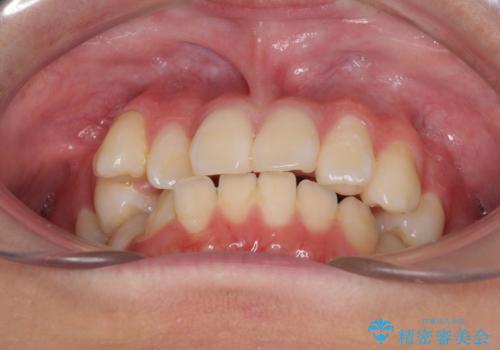

- 八重歯を気にして来院された高校生の患者様です。

ボディーコンタクトの激しい部活動を行っているため、補助装置とインビザラインを用いて、部活動を継続しながら治療を行うこととしました。

八重歯を効率よく改善するため、補助装置を使用して上顎の奥歯を後方に移動させました。

部活動をしながらでしたが、マウスピースをしっかりと装着してくださったので、1年半程度で終了することができました。